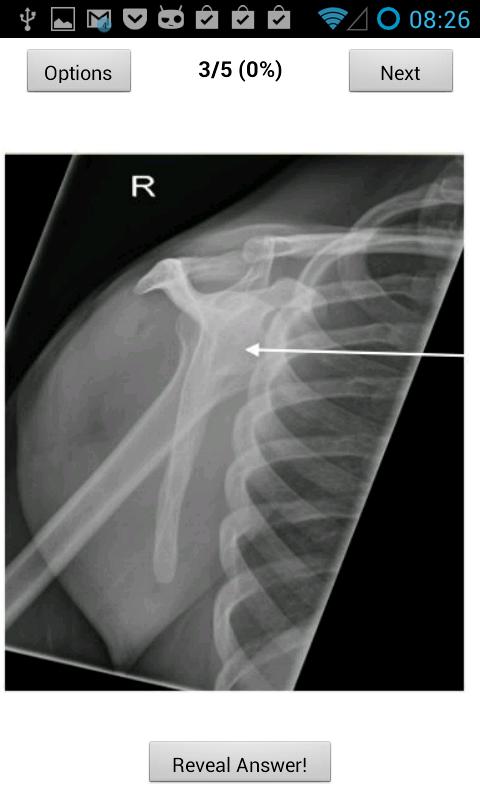

Это приложение помогает кандидатам на радиологию, проведя экзамен по анатомии FRCR. Он содержит 60 бесплатных вопросов в стиле экзамена, каждый из которых имеет одну этикетку (согласно вопросам 2013 года) с возможностью покупки еще 240 вопросов *** только 0,50 фунтов стерлингов за ограниченное время ***

* Позволяет вам нацелиться на ревизию анатомии с помощью анатомической области.

* Ущипнуть, чтобы увеличить

* Подробное отслеживание вашего прогресса, включая составление графика вашего среднесуточного, среднего знака и сколько вопросов.